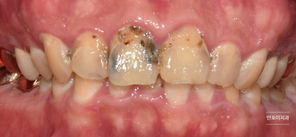

앞니 충치를 치료하러 오신 환자분 (심미보철수복) (Treatment of tooth decay & Esthetic zirconia crown restoration)

안녕하세요 반포이치과 이윤섭입니다 오늘은 외국에서 생활하시는 분으로, 멀리서 오신 귀한 손님이 오셨습니다. 오랫동안 치과진료를 받지 못하셔서, 치료해야할 곳이 많았는데요. 앞니 충치가 심하게 진행된 상황입니다 미관상으로도 많이 훼손된 모습입니다...